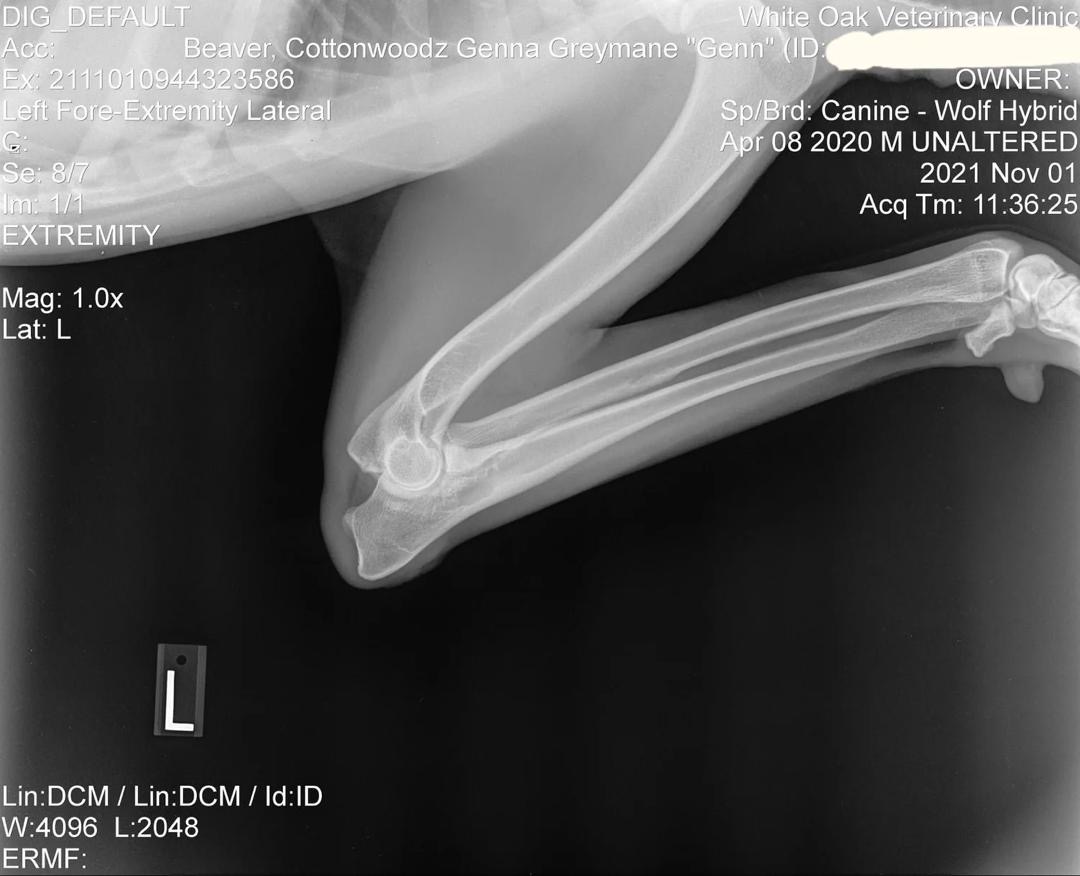

Genn Preliminary Left Elbow X-Ray

Preliminary Left Elbow X-Ray

Early evaluation: Normal formation